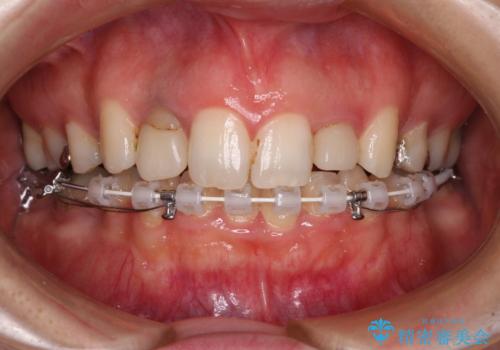

飛び出した上顎前歯とむし歯の多い歯列 目立たないハーフリンガル矯正とむし歯治療

- 上顎前歯が叢生により前方に出ている状態や、全体的なむし歯を気にして来院された患者様です。

全体的にむし歯や欠損が多く、矯正治療とは別に処置が多く必要な口腔内でした。

目立たないハーフリンガル矯正を希望され、裏側装置はどうしても清掃性が低下し、むし歯発生のリスクが高まるため、矯正治療前にしっかりとむし歯治療を行い、矯正治療後にセラミックによる補綴治療を行うこととしました。

抜歯したスペースがなかなか閉じず、治療に時間はかかりましたが、術前術後のむし歯治療と合わせて3年10ヶ月で治療を終えることができました。